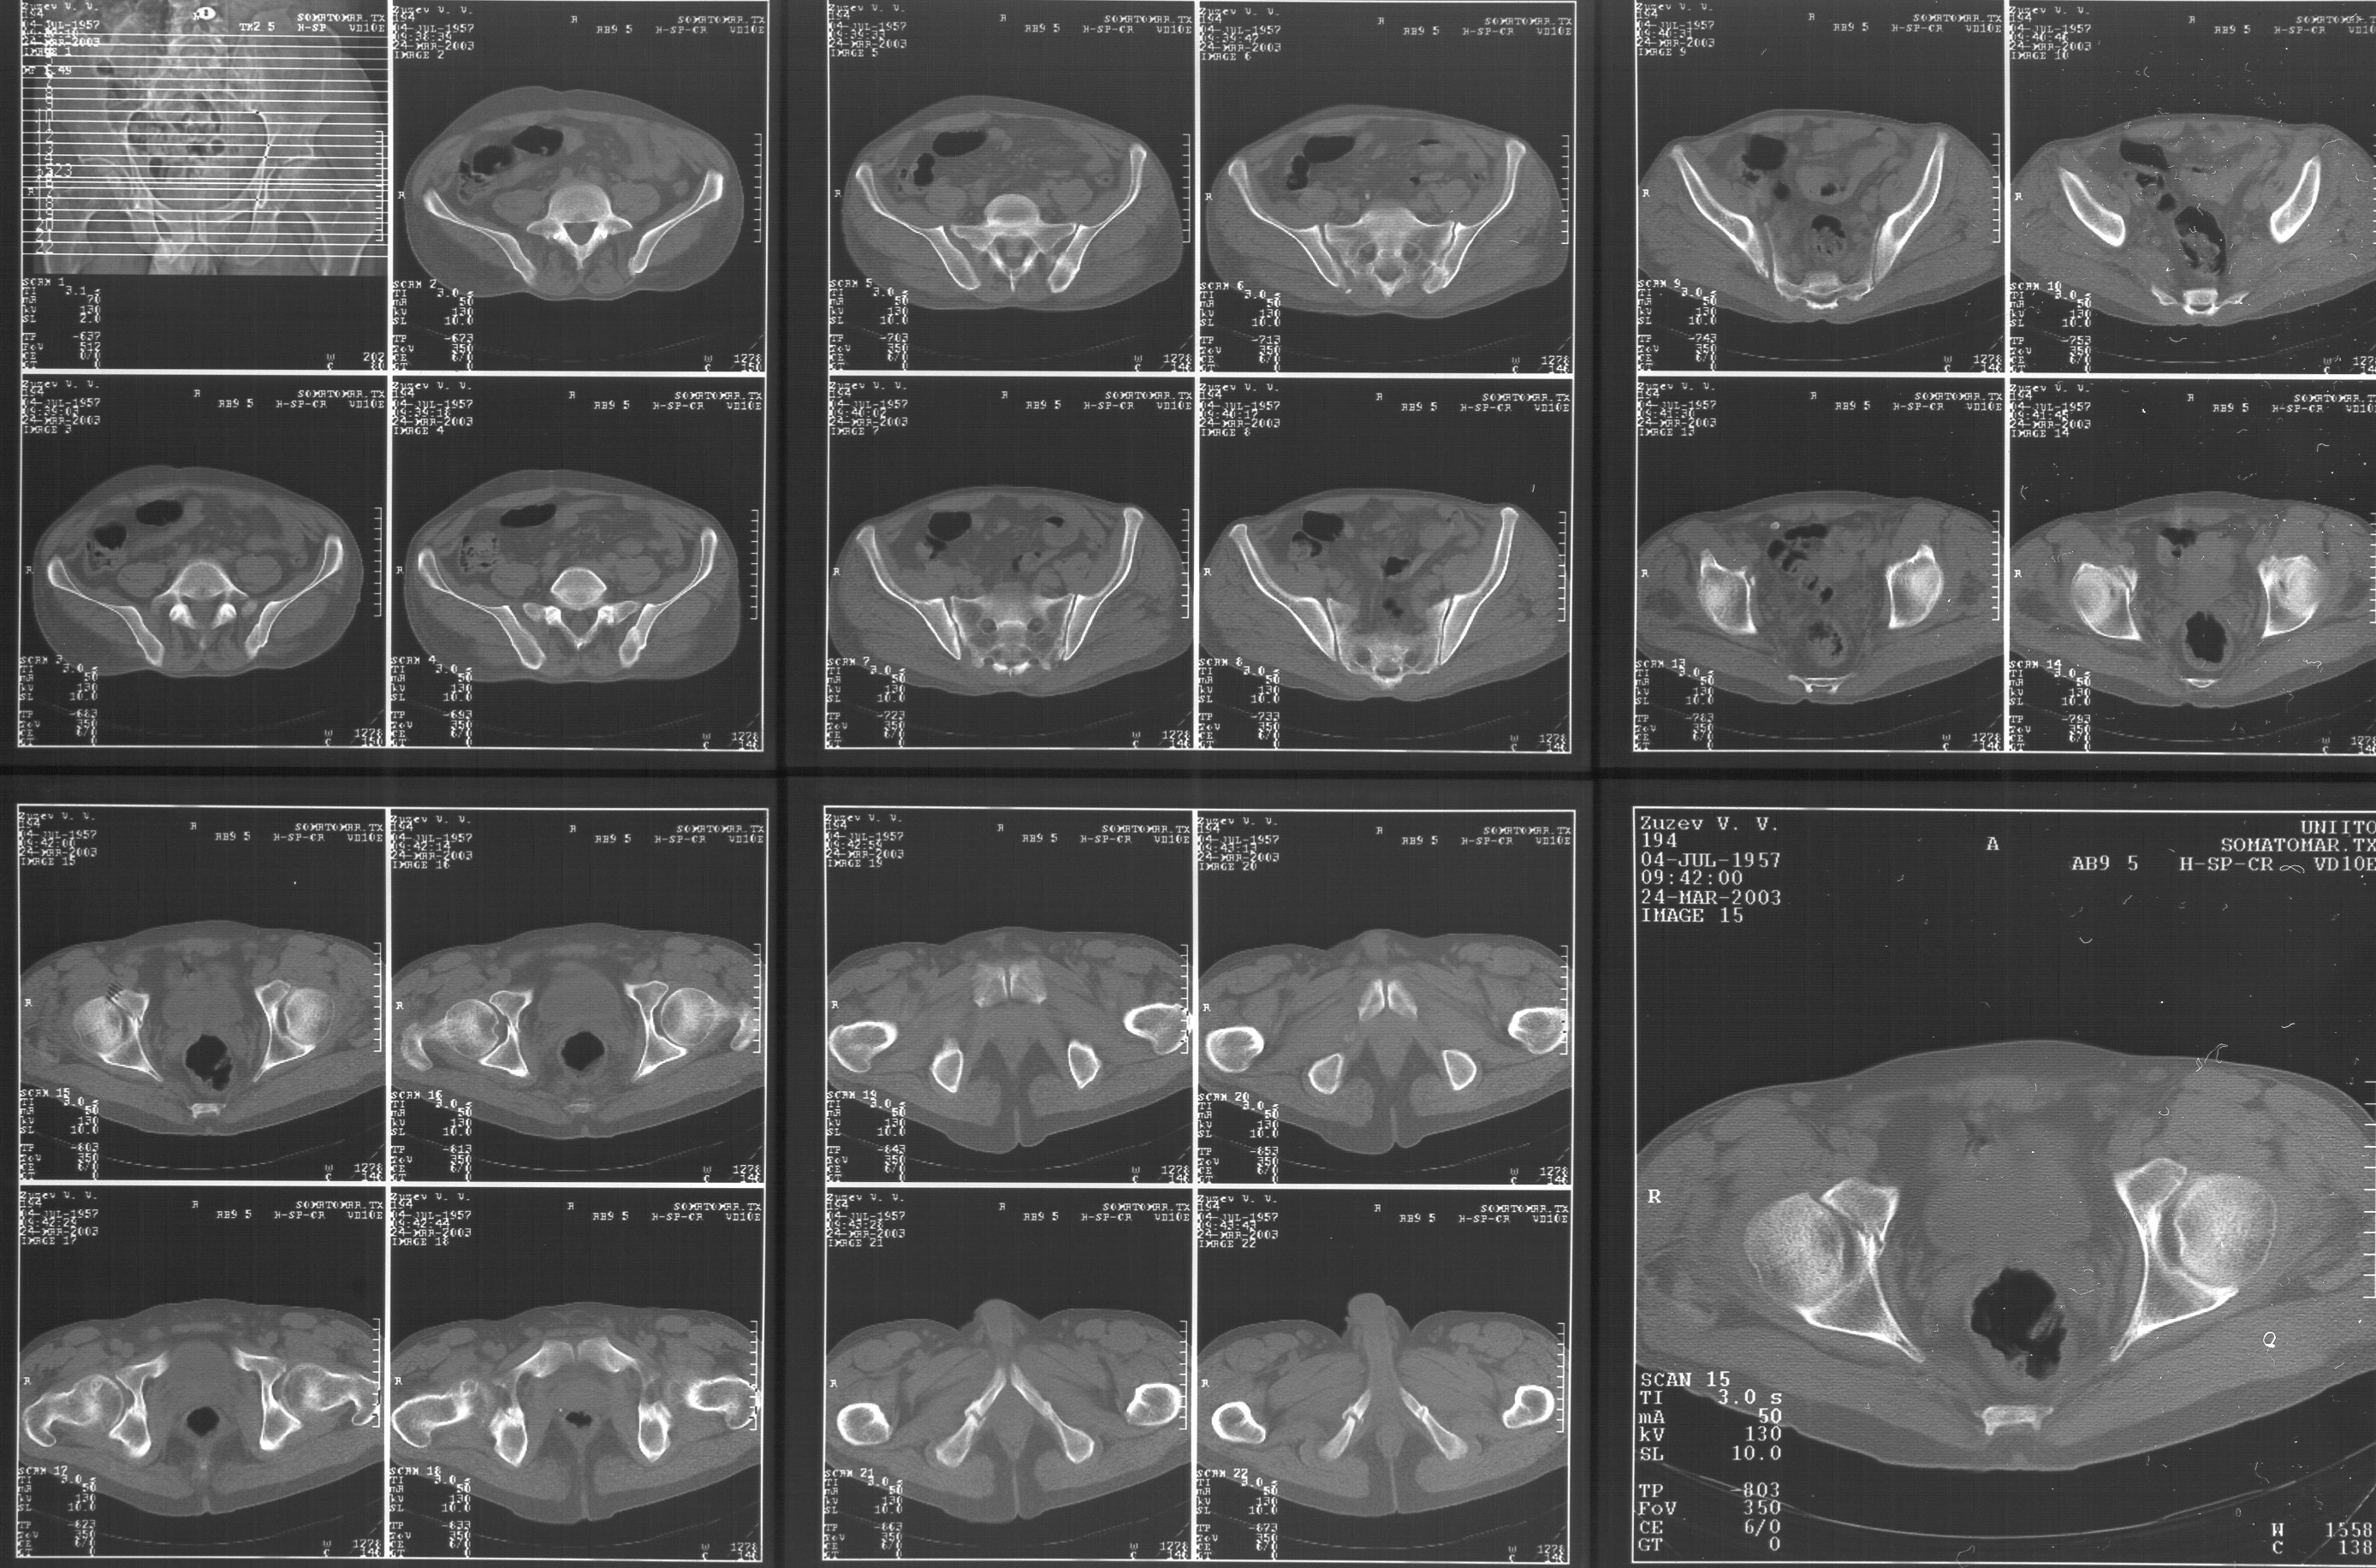

Прилагаю свежую КТ таза.

Буду признателен за комментарии и предложения по тактике.

Картинки см. ниже, левая - с экранным разрешением, вторая - полноразмерная, ~900 кб.

КТ в экранном разрешении